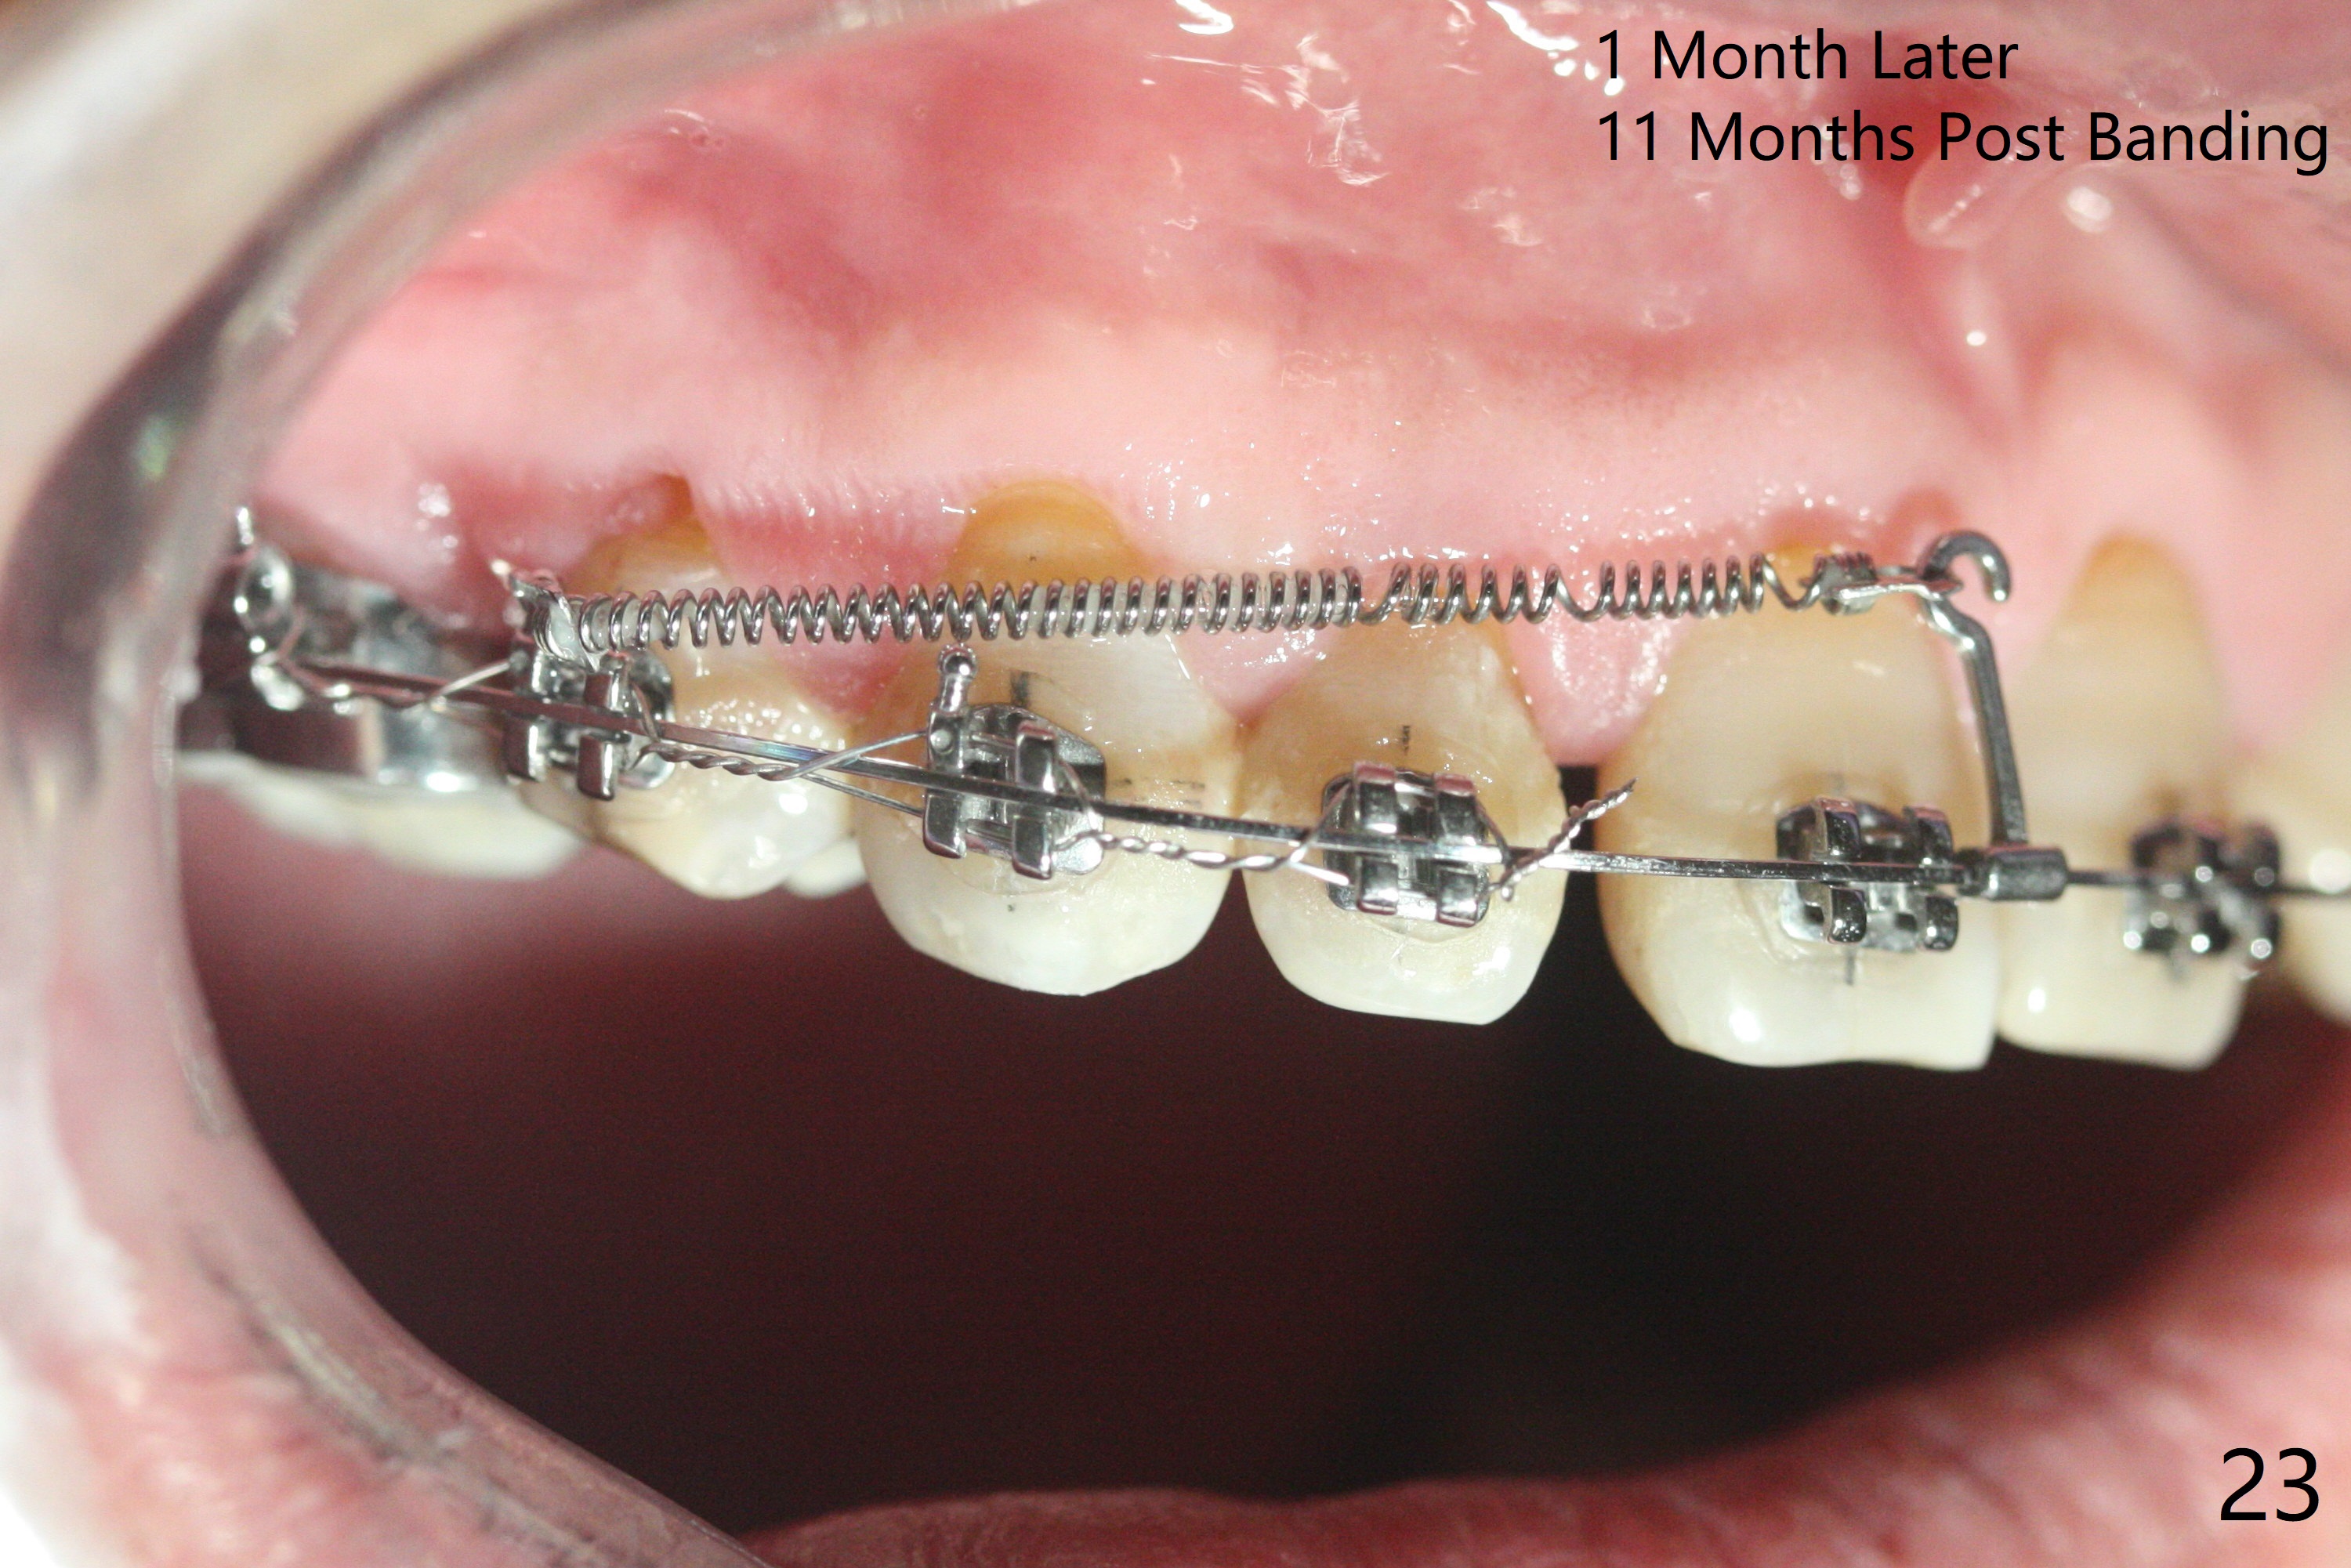

A 40-year-old man requests orthodontics after #17 and 32 extraction. UL5 is missing (Fig.1), while the upper midline deviates to the left (Fig.2 arrow) with crowding between UL2 and 3 (Fig.3). The main goal is to retract UL5 distal and move the upper midline to the right to alleviate UL anterior crowding. Implant will be not needed. To monitor potential root resorption associated with tooth movement, preop PAs are taken (Fig.4-7). The space for an implant at UR5 is narrow. UR4 needs to be distalized using UR7 or a miniimplant distal to UR7 as an anchor (Fig.8). UR4 and 3 will be repositioned to establish Class I occlusion (Fig.9). The space gained by UR4 distalization may be enough to correct the upper midline deviation and UL3 malposition (Fig.10). Brackets will be placed in the lower arch in spite of the normal alignment (Fig.11). UL2 and 3 brackets are unable to be engaged to 14 niti wire (Fig.12). Next visit try to engage UL2 bracket. If not, save the old wire for possible future reuse. Closed spring is placed with 18 ss wire <3 months post banding (coronavirus). Three weeks post closed spring between UR4-7, UR3,4 are being distalized (Fig.13). Distalization of UR4 is not much in 5.5 months (Fig.14,15). It seems necessary to use a miniimplant distal to UR7 as an anchor (Fig.16 white circle), place a long hook mesial to UL4 (more or less root movement instead of tilt) and place the same closed spring between the anchor and hook. In spite of the fact that UR4 seems to have been completely distalized and that UR2 is being distalized 8 months post banding (Fig.18), a 8 mm long mini-implant is placed in the maxillary tuberosity with minimal local anesthetic (Fig.17,19). A longer closed spring (18 mm) is placed between the implant and UR3 hook (Fig.20). Next appointment a lingual button will be placed at UR4 for rotation, while a post hook mesial to UR3 for torque. UR3 distalizes with the help of UR mini-implant, which is unfortunately loose. Next visit place lingual button at UR4 (Fig.21 arrow) to distalize the lingual cusp. Crimpable power hook is placed mesial to UR2 for distalization (for root torque, Fig.22). If it works, remove the wire and reposition the hook for UR1 next visit. UR2 is distalized in one appointment (~ 1 month, Fig.23, as compared to Fig.22). With lingual button at UR4, rotation seems to have been corrected shortly (Fig.24 arrow).